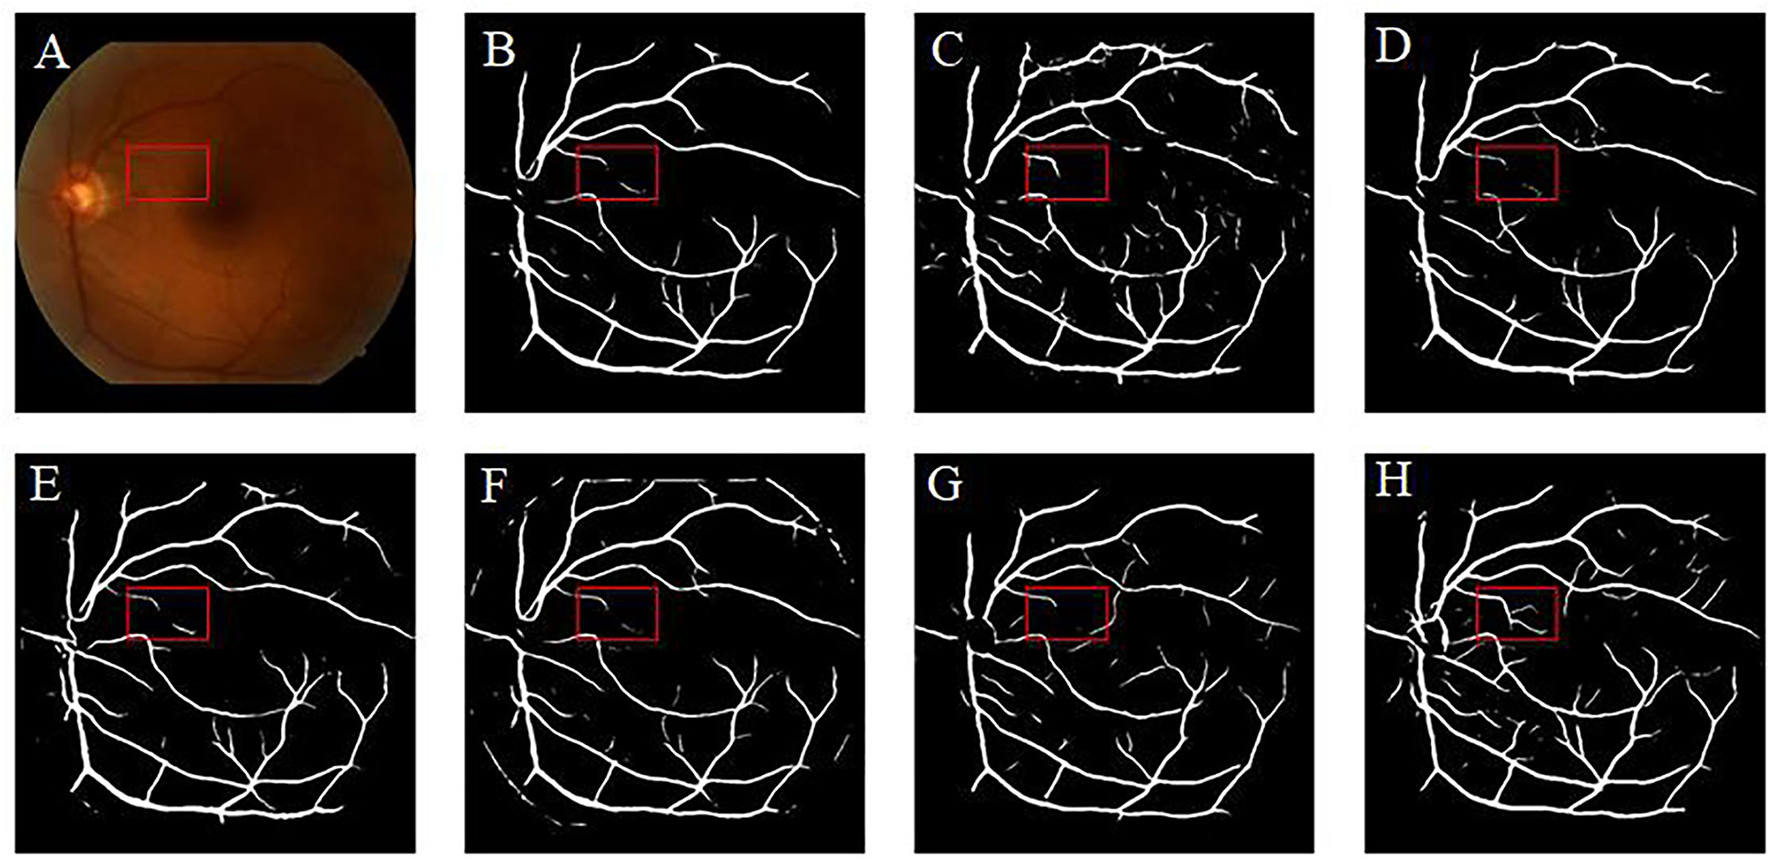

Retinal vessel segmentation is crucial for the screening of eye diseases. To verify the effectiveness of image enhancement, we applied the enhanced retinal images to the retinal vessel segmentation task. Figure 12A shows the low-illumination retinal image, where only a few large vessels were recognized with short vessel lines (Figure 12B). Images enhanced by CycleGAN (Figure 12G) and Cycle-CBAM (Figure 12H) can be segmented into complete blood vessels. In Figure 12G, there are some messy thin blood vessels, which are not continuous. This may be caused by the misidentification of noise in the enhanced image. Figure 12H can accurately segment the thick and thin blood vessels. The veins are coherent and can reveal the true structure of blood vessels. Figure 13 demonstrates the results of retinal vessel segmentation of blurred image and images enhanced by different methods. Figure 13B shows only the main blood vessels, which can also be easily identified by the naked eye in Figure 13A. The results of the enhanced images (Figures 13C–G) show more blood vessels, but the segmentation of small vessels is insufficient. By comparing the red boxes at the same position in each subgraph, only the proposed method (Figure 13H) can clearly display the complete vessel structure and show the small vessels in the red box, which indicates the successful application of the proposed method in retinal vessel segmentation and the effectiveness of our enhancement method.

Figure 12

Results of retinal vessel segmentation in the low-illumination and enhanced images by different methods. (A): Low-illumination image. (B): Segmentation result of the low-illumination image. (C–H): Segmentation results of images enhanced by different methods. [(C): CLAHE. (D): Fusion-based. (E): MSRCP. (F): LIME. (G): CycleGAN. (H): Ours].

Figure 13

Results of retinal vessel segmentation in the blurred and enhanced images by different methods. (A): Blurred image. (B): Segmentation result of the blurred image. (C–H): Segmentation results of images enhanced by different methods. [(C): CLAHE. (D): Fusion-based. (E): MSRCP. (F): LIME. (G): CycleGAN. (H): Ours].